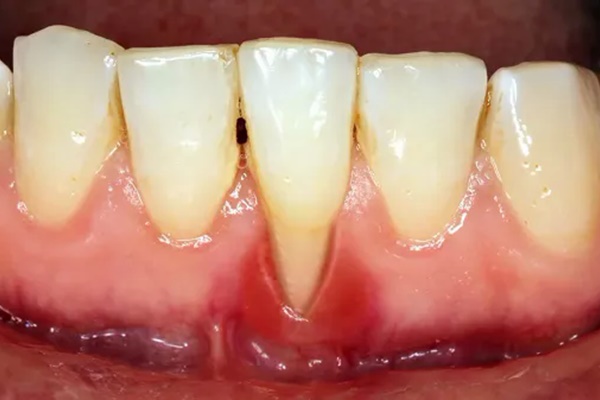

Với trường hợp tiêu xương do viêm nha chu bởi vì nướu răng bị viêm gây tụt nướu (tụt lợi) làm hở chân răng, từ đó sẽ dẫn tới tình trạng xương và dây chằng bao bọc quanh răng bị tiêu hủy dần, khiến răng không còn chỗ dựa gây nên tiêu xương hàm.

Hình ảnh tiêu xương do viêm nha chu